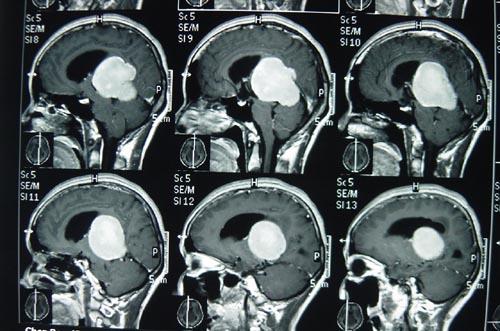

腦膜瘤如何治療不易復(fù)發(fā)?2016年美國腦腫瘤注冊中心(Central Brain Tumor Registry of the United States,CBTRUS)統(tǒng)計(jì),腦膜瘤約占顱內(nèi)腫瘤的36.6%。根據(jù)國際衛(wèi)生組織(World Health Organization,WHO)2016版中樞神經(jīng)系統(tǒng)腫瘤分類的定義,按照分子病理學(xué)、有無腦實(shí)質(zhì)的侵犯等特點(diǎn),可將腦膜瘤分為WHO Ⅰ級(jí)、WHO Ⅱ級(jí)(不典型)、WHOⅢ級(jí)(間變型)。

既往研究表明,WHOⅠ級(jí)的腦膜瘤占80%~90%,為良性腫瘤,其生長緩慢,術(shù)后不易復(fù)發(fā),預(yù)后好于WHO Ⅱ級(jí)及Ⅲ級(jí)。新版WHO中樞神經(jīng)系統(tǒng)腫瘤分類將侵犯周圍腦組織的腦膜瘤定義為WHO Ⅱ級(jí)(不典型),故其占比有增高趨勢,約為10%~15%;作為預(yù)后較差的WH O Ⅲ 級(jí)腦膜瘤(約占1%~3%),5年復(fù)發(fā)率高達(dá)90%,10年總生存率幾乎為零。

腦膜瘤如何治療不易復(fù)發(fā)?腦膜瘤目前主要依靠手術(shù)治療,但部分腦膜瘤患者為偶然發(fā)現(xiàn),并無癥狀;而不同部位,是位于顱底的腦膜瘤因周圍解剖結(jié)構(gòu)復(fù)雜,病灶與神經(jīng)關(guān)系密切,使手術(shù)操作變得困難;另外,還有部分腦膜瘤患者年齡較大,手術(shù)獲益與風(fēng)險(xiǎn)需要權(quán)衡。對(duì)于以上情況的腦膜瘤,如果術(shù)前能夠判定腫瘤為良性,多可考慮保守的治療策略。因此,術(shù)前影像學(xué)評(píng)估腦膜瘤的分級(jí)有著重要的臨床價(jià)值。